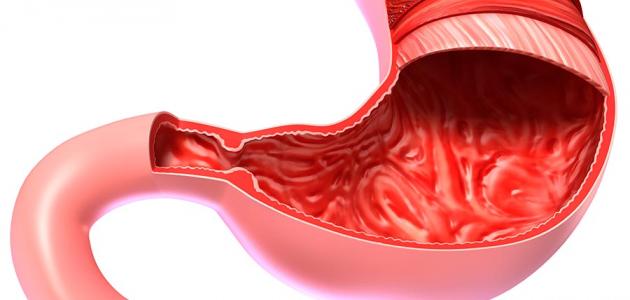

يُعرف التهاب القولون طبياً بالتهاب القولون التقرحيّ (بالإنجليزية: Ulcerative colitis)، وهو أحد نوعين رئيسيين من مرض التهاب الأمعاء (بالإنجليزية: Inflammatory bowel disease)، حيث يُعرف النوع الثاني من مرض التهاب الأمعاء (بالإنجليزية: Crohn’s disease). ويُعتبر كلا المرضين من الأمراض المزمنة التي تستمر مدى الحياة، وتجدر الإشارة إلى أنّ مرض التهاب الأمعاء يختلف تماماً عن (بالإنجليزية: Irritable bowel syndrome) الذي يؤثر في وظيفة الأمعاء دون وجود التهاب. ويؤثر التهاب القولون التقرحي في الفئات العمرية المختلفة إلا أنّه يبدأ عادة بين سن 15 و30 عاماً، كما أنّه يُلاحظ بشكل واضح لدى الأشخاص بين عمر 50 و70 سنة، وتُعدّ إصابة أحد أفراد الأسرة المقربين بالتهاب القولون التقرحي عامل خطر يزيد فرصة إصابة باقي أفراد الأسرة بالمرض ذاته، وقد يكون من الصعب في بعض الأحيان التمييز بين التهاب القولون التقرحي ومرض كرون، لا سيما في المراحل المبكرة، إذ إنّ الأعراض تكون متشابهة بشكل كبير. وتتمثل الفروقات الأساسية بين المرضين في أنّ التهاب القولون التقرحي لا يؤثر إلا في البطانة الداخلية لجدار الأمعاء، أما في حالة مرض كرون فإنّ الالتهاب يؤثر في جدار الأمعاء بالكامل، ويؤثر التهاب القولون التقرحي في المتمثلة بالقولون والمستقيم فقط، بينما يمكن لمرض كرون أن يؤثر في أي جزء من الجهاز الهضمي بدءاً من الفم وانتهاء بفتحة الشرج.

قد تختلف علامات وأعراض التهاب القولون التقرحي اعتماداً على مرحلة المرض وموقعه، لكنّ الأعراض الأكثر شيوعاً تضم تقرحات بطانة الأمعاء الغليظة، والبراز المصحوب بالدم، وألم البطن والتشنجات، والإسهال، والشعور المُلِحّ بِضرورَة التَّغَوُّط مع عدم القدرة على ذلك، وهذا ما يُعرف طبياً بالزحير أو الزحار (بالإنجليزية: Tenesmus)، ومن الأعراض الأخرى: الحُمّى، وفقدان الشهية، . وتجدر الإشارة إلى أنّ التهاب القولون التقرحيّ يُعدّ مرضاً تقدمياً، وهذا يعني أنّ التقرحات قد تبدأ في الجزء الأخير من الأمعاء الغليظة، والذي يُعرف بالقولون السينيّ، ثم قد تنتشر إلى باقي أجزاء القولون. وتضمّ الأشكال المختلفة من التهاب القولون التقرحي الأكثر شيوعاً ما يأتي: